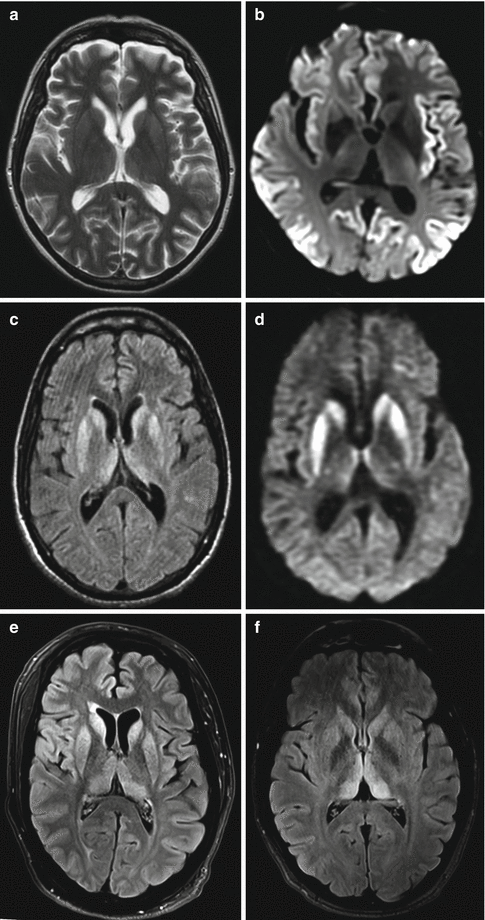

Prion Diseases Neupsy Key This article presents an update on the clinical aspects of human prion disease, including the wide spectrum of their presentations. Prion, an abnormal form of a normally harmless protein found in the brain that is responsible for a variety of fatal neurodegenerative diseases of animals, including humans, called transmissible spongiform encephalopathies. Prion diseases (or transmissible spongiform encephalopathies) are a group of uniformly fatal neurodegenerative diseases characterised by progressive dementia and motor dysfunction. these diseases occur in spontaneous, genetic, and acquired forms. Prion diseases are rare, fatal neurodegenerative disorders caused by misfolded prion proteins in the brain. learn about the different types of prion diseases, how they affect humans and animals, and what treatments are available. Overview of prion diseases etiology, pathophysiology, symptoms, signs, diagnosis & prognosis from the merck manuals medical professional version. Prion disease represents a group of conditions that affect the nervous system in humans and animals. explore symptoms, inheritance, genetics of this condition.